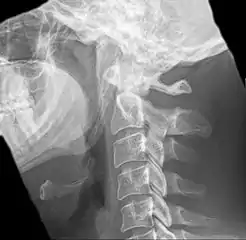

Anteroposterior and lateral radiographs of cervical spine showing ossification of the stylohyoid ligament on both sides

Eagle syndrome occurs due to elongation of the styloid process or calcification of the stylohyoid ligament, potentially compressing the nearby carotid arteryor glossopharyngeal nerve.[4] However, the cause of the elongation hasn’t been known clearly. It could occur spontaneously or could arise since birth. Usually normal stylohyoid process is 2.5–3 cm in length, if the length is longer than 3 cm, it is classified as an elongated stylohyoid process.[10] There are reports of eagles syndrome been elicited after wisdom tooth removal. [11]

Imaging is important and is diagnostic. Visualizing the styloid process on a CT scan with 3D reconstruction is the suggested imaging technique.[12] The enlarged styloid may be visible on an orthopantogram or a lateral soft tissue X ray of the neck.